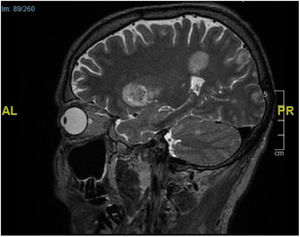

Supplementary testsTwo skin biopsies were performed on a plaque and a subcutaneous nodule. Histopathology examination confirmed a substantial presence of elongated and septate hyphae across the dermis and epidermis and up to the stratum corneum (Fig. 2A). Extensive panniculitis-like fat necrosis and hyphae inside the adipose tissue were also noted (Fig. 2B). Before mycological confirmation, the patient became obtunded. The emergency CT scan of the brain revealed the presence of parenchymal lesions consistent with septic emboli. Subsequent magnetic resonance imaging (Fig. 3) confirmed the findings.